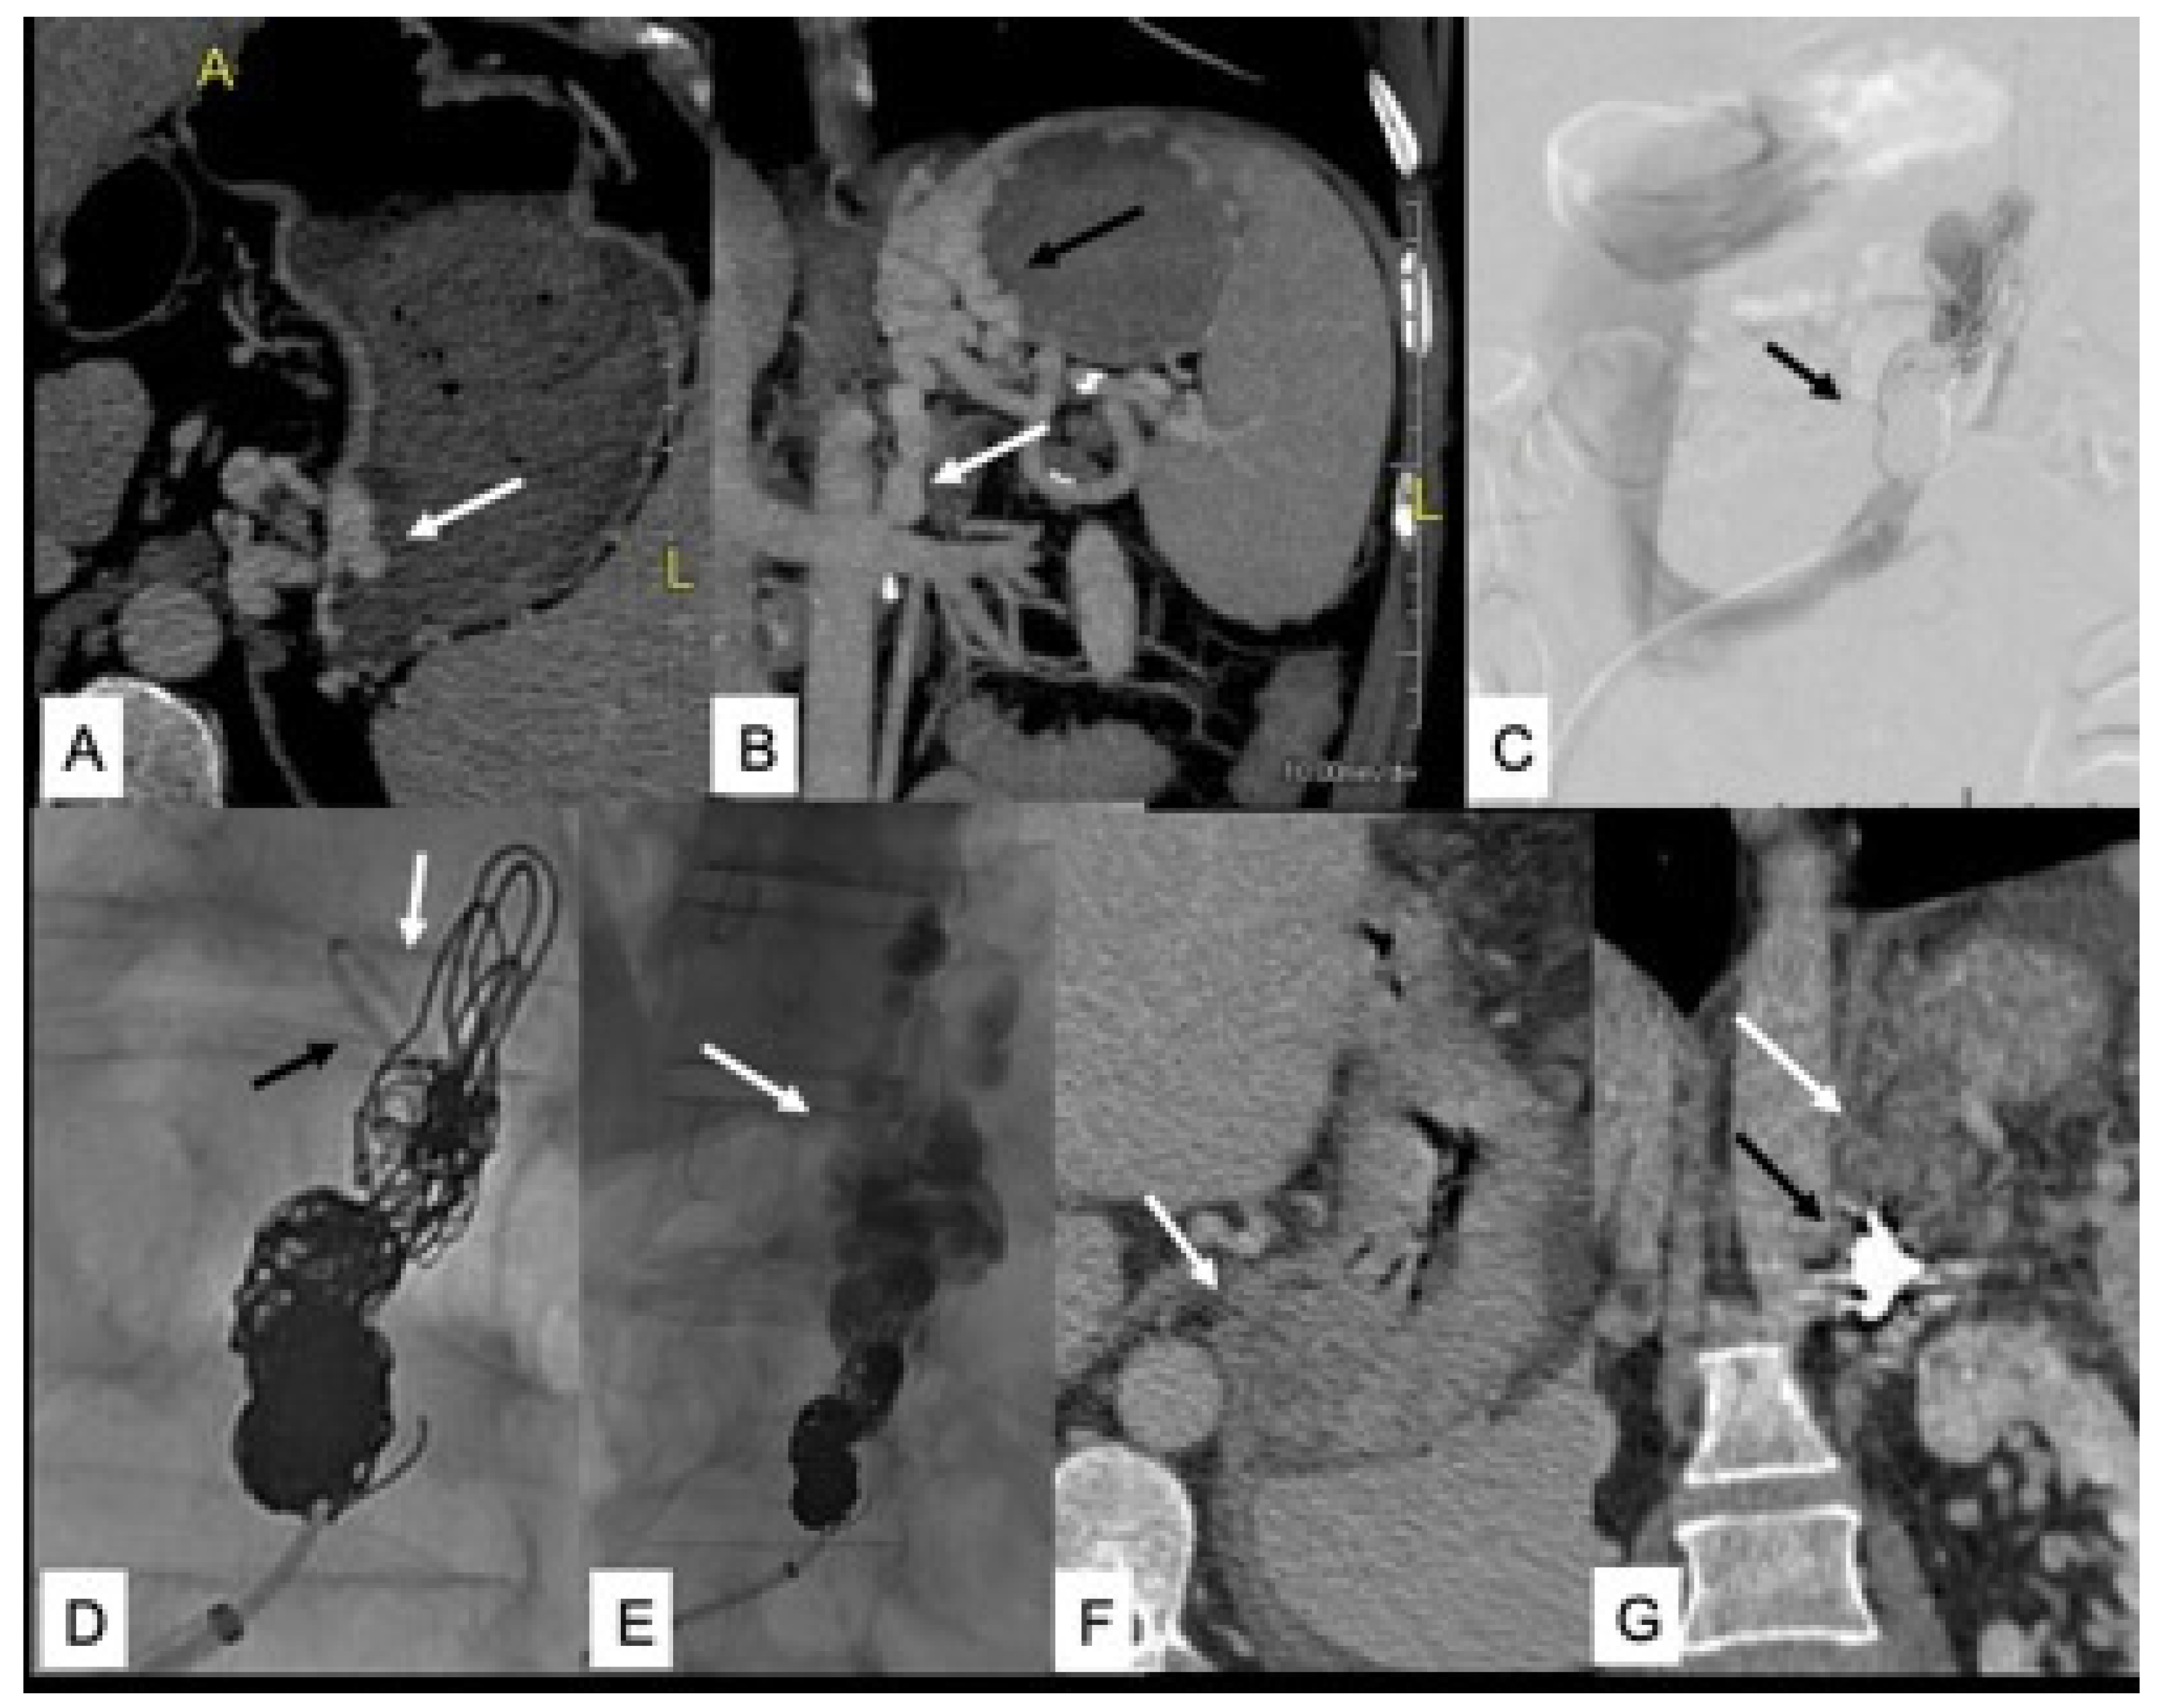

- Nardelli, S.; Gioia, S.; Ridola, L.; Riggio, O. Radiological Intervention for Shunt Related Encephalopathy. J. Clin. Exp. Hepatol. 2018, 8, 452–459. [Google Scholar] [CrossRef]